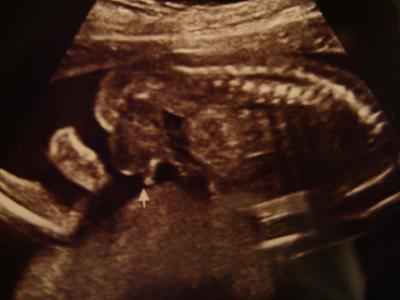

Hallo Mädels! Also es bleibt dabei....es wird ein Bub! Beweisfoto im Anhang! Das muss man einfach erkennen. Er ist zeitgemäß entwickelt und seine Organe ohne Auffälligkeiten. Gewicht und Größe konnte er mir nicht sagen. Nur das er bei 21/22 mm liegt. Hab mich schon total in ihn verliebt. Ein hübscher Junge. Nur mein Gebärmutter Puls (glaube so hieß es) wäre nicht so toll (irgendwas ist ja immer) Muss jetzt Blutverdünner nehmen, weil der Mutterkuchen jetzt dabei wäre sich richtig aufzubauen und da braucht es wohl die Unterstützung dazu. Sein Herz konnte er auch nicht richtig sehen, da er mit dem Rücken zu uns lag. In 4 Wochen darf ich nochmal kommen und dann schaut er sich nochmal das Herz und den Puls an. Dann waren wir endlich Heim und er hat mich dann getreten, damit ich mich endlich mal hinlege.... ...aber Auto fahren fand er toll, nur anhalten war im zu langweilig

Bild zu Heute FD Termin - Forum für August - Mamis

Klasse das alles in Ordnung ist und ein wirklich eindeutiges Beweisfoto hast du da bekommen... LG Nici

Freut mich, dass bei euch soweit alles in Ordnung ist. Das mit dem "Puls" kommt bestimmt wieder ganz in Ordnung und die Blutverdünner helfen dabei. Glückwunsch zum Buben (tolles Beweisfoto - sehr eindeutig )